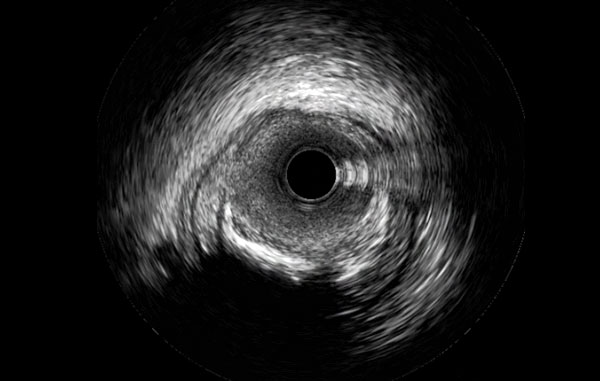

Coronary Imaging